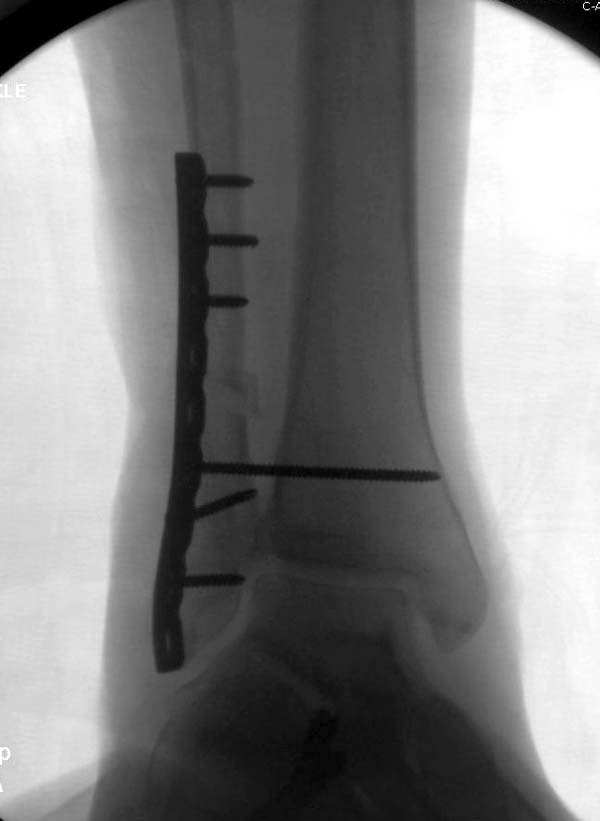

Здесь представлено решение похожей проблемы. Больной в течение года лечился консервативными мерами, и боли в голеностопе были основным показанием к операции.

Проведена обычная стандартная процедура по исправлению неудовлетворительного состояния голеностопного сустава, где кроме удлинения малоберцовой с применением compression tension device за проксимальный конец пластины, проведено замещение трикортикальным графтом из крыла, освобождение синдесмоза и медиальной щели от

фибротических масс с фиксацией.

Дополнительно у больного плоская стопа, во время операции провели небольшую скользящую остеотомию, надеемся, что поможет.